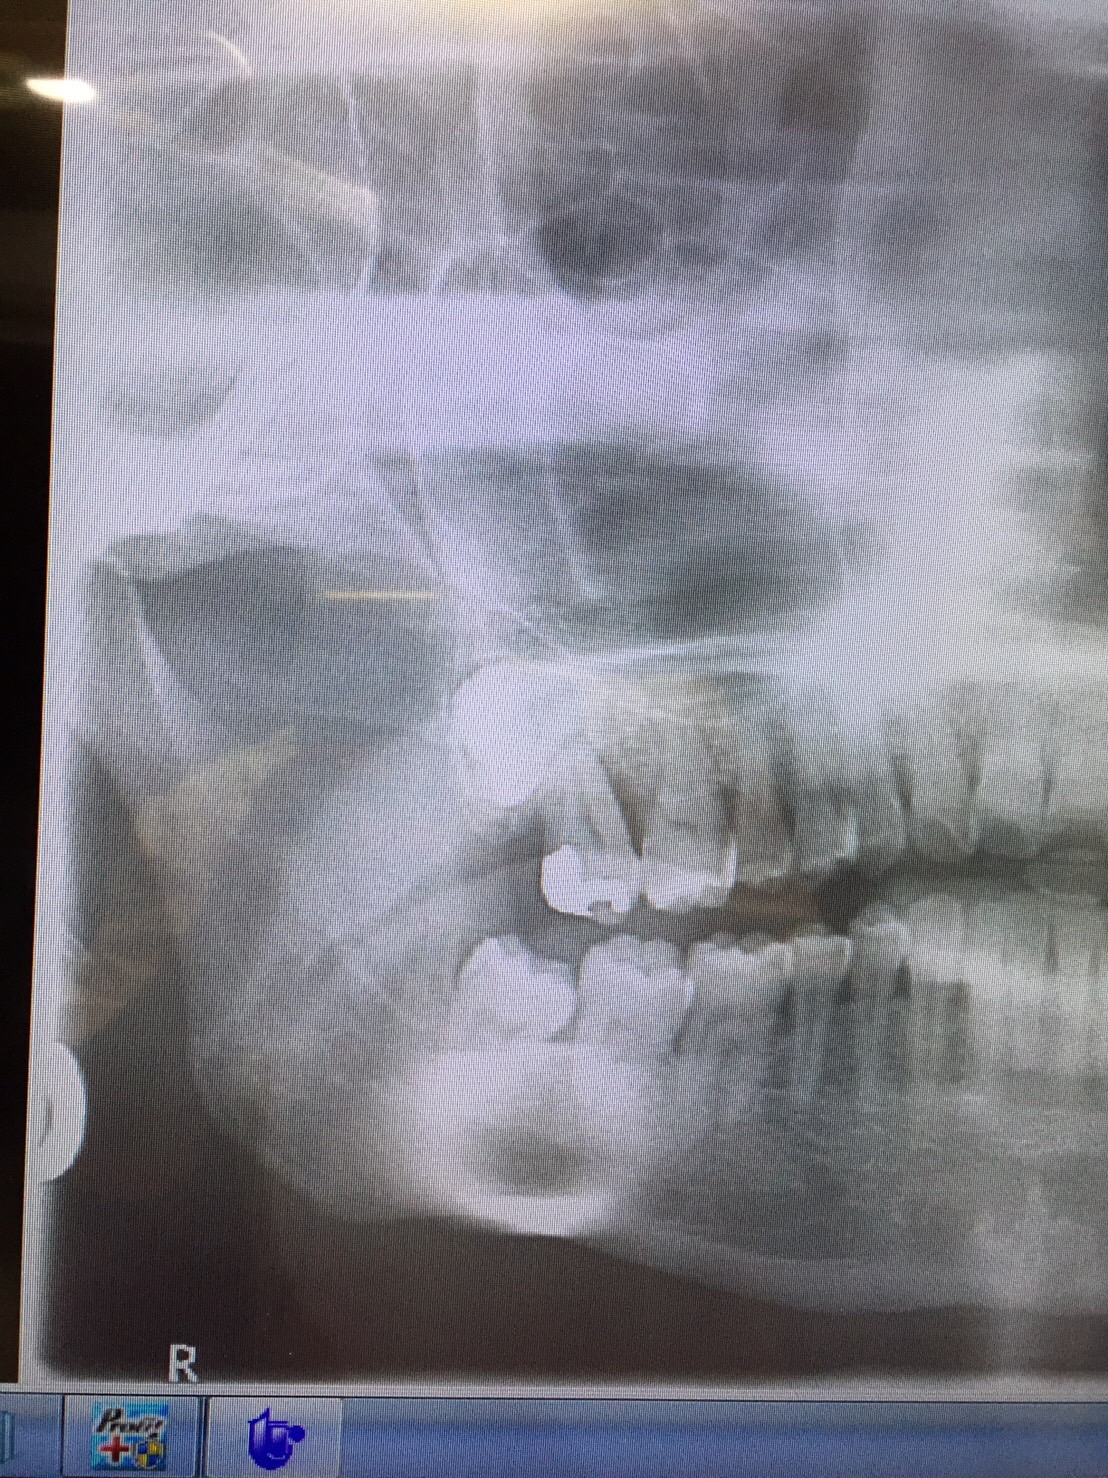

こんばんわ! 2/8に右下の親知らずの抜いてから2日経ちましたが、

抗生物質と鎮痛剤をちゃんと飲んでいたら全く痛くないです。

今日、衛生士さんに消毒してもらいましたが傷口もとても綺麗ですよ〜と! しかもほとんど腫れることもなかったです。